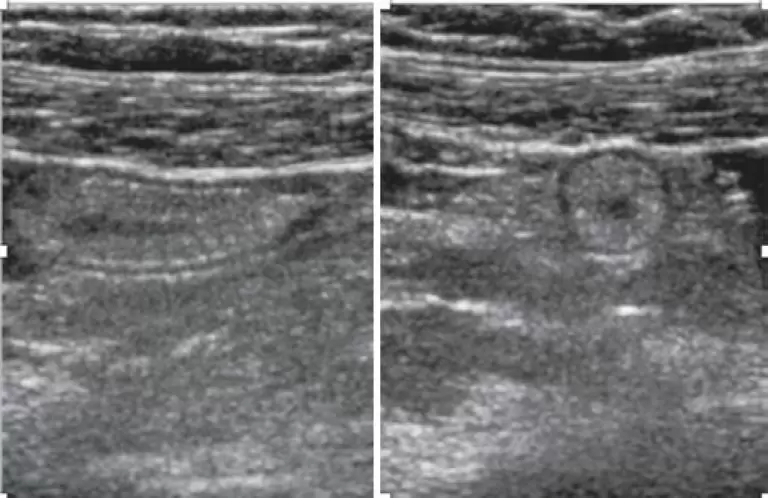

RESUMO Paciente de 34 anos, do sexo feminino, grávida, chega ao pronto-socorro com queixa de dor na fossa ilíaca direita piorando nos últimos 2 dias com suspeita de apendicite aguda. Foram solicitados exames laboratoriais, que estavam dentro dos limites de normalidade para aspectos infecciosos e inflamatórios. Exame de imagem também foi solicitado, sendo a ultrassonografia o método de escolha, que revelou gravidez em curso sem alterações e espessura da parede do apêndice sem sinais inflamatórios. Ainda com suspeita de apendicite […]